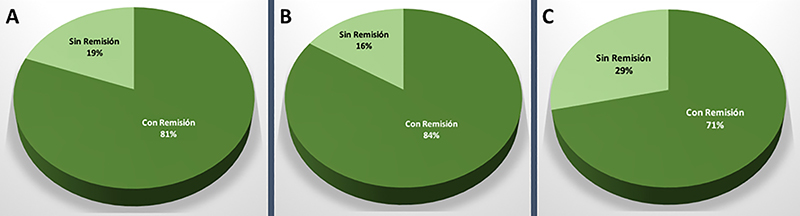

En los pacientes con enfermedad de Cushing (n=26), de los cuales 19 eran microadenomas y 7 macroadenomas, se logró con la cirugía una tasa de remisión bioquímica global del 81% (n=21); siendo la remisión para microadenomas del 84% (n=16) y para macroadenomas del 71% (n=5) (graf. 4). Los pacientes sin remisión se encuentran bajo terapia multimodal.

Gráfico 4: Resultados en pacientes con Enfermedad de Cushing. A: Remisión bioquímica global. B: Remisión bioquímica en el caso de los microadenomas. C: Remisión bioquímica para los macroadenomas.

En los pacientes con prolactinomas (n=21), de los cuales 9 fueron microadenomas y 12 macroadenomas, se logró con la cirugía una remisión bioquímica global del 71% (n=15); siendo la remisión para microadenomas del 100% (n=9) y para macroadenomas del 50% (n=6) (graf. 5). Los 6 pacientes con hiperprolactinemia activa se encuentran en seguimiento bajo tratamiento multimodal. De estos, 4 pacientes presentaron un Knosp alto preoperatorio.

Gráfico 5: Resultados en pacientes con prolactinoma. A: Remisión bioquímica global. B: Remisión bioquímica en el caso de los microadenomas. C: Remisión bioquímica para los macroadenomas.

En una serie de 426 cirugías hipofisarias primarias en pacientes con enfermedad de Cushing, el Prof. Fahbulsh logró encontrar tumor durante la cirugía en un 86,6% (n=369) pacientes. En estos, se practicó una adenomectomía selectiva, obteniendo una remisión global del 75,9% (n=280) pacientes.35

Al evaluar las tasas de remisión en la misma serie, considerando el tamaño tumoral se evidencia la misma fue: del 77,9% para microadenomas y 59% en macroadenomas.35

Gondim et al. publicaron una seria de 228 pacientes operados por vía baja, de los cuales 28 presentaron enfermedad de Cushing. De estos, se logró la remisión en un 75% de los microadenomas y un 62,5% de los macroadenomas.34

En nuestra serie se alcanzó una tasa de remisión: global del 81%, para microadenomas del 84% y para macroadenomas del 71%. La tasa global y para microadenomas es equiparable a la publicada por equipos de referencia. La alta tasa de remisión en macroadenomas respecto a la literatura se explica por un sesgo estadístico (N reducido de pacientes con macroadenoma y enfermedad de Cushing).

Respecto a la tasa de remisión global, Jho et al. reportaron un 71%.38 En cuanto a la tasa de remisión según el tamaño, en una compilación de series publicadas, la tasa de normalización de PRL fue de 83% en microprolactinomas57 y 45.1% en macroprolactinomas1.

De lo antes expuesto, queda en evidencia que la cirugía ofrece excelentes resultados de tasa de normalización de prolactina en el caso de los microprolactinomas.9

En la presente serie la tasa de remisión global fue del 71%; mientras que la tasa de remisión según tamaño fue 100% para microadenomas y 50% para macroadenomas. Estas cifras pueden homologarse a la de las publicaciones enunciadas en este apartado. La alta tasa de normalización de la PRL obtenida en microprolactinomas se explica debido a que estos pacientes presentaron tumor central a la glándula y no lateralizado.